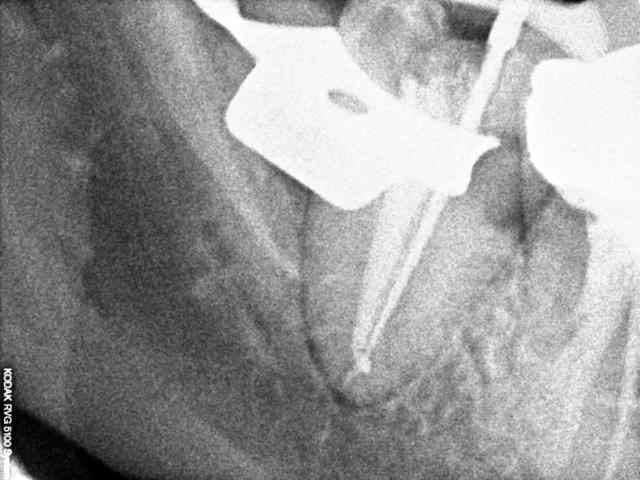

Un patient se présente avec une lésion carieuse importante sur 47. Je fait une rétroalvéolaire. La forme de l'endodonte m'interpelle, je curete et ne fait pas d'effraction pulpaire, donc je met un CVI. Le patient fait une pulpite, je fait le traitement, j'ai trouvé un très gros canal distal que je pensais unique, puis un tout petit mésial bien centré dans le sens linguo vestibulaire.

Ai-je tout obturé?

Un cas traite l'an dernier et pas de pb a ce jour ...